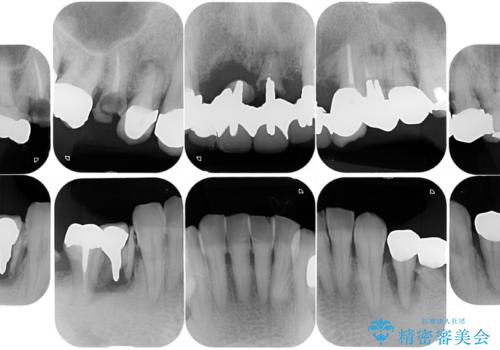

- お孫さんに口臭を指摘されたことで治療を決断し、来院されました。

歯周病、虫歯、合わない被せ物がニオイの原因となっていたため、そのすべてを治療することになりました。

まずは歯周病の治療と抜くしかない歯を抜き、インプラント治療とセラミック治療を行いました。